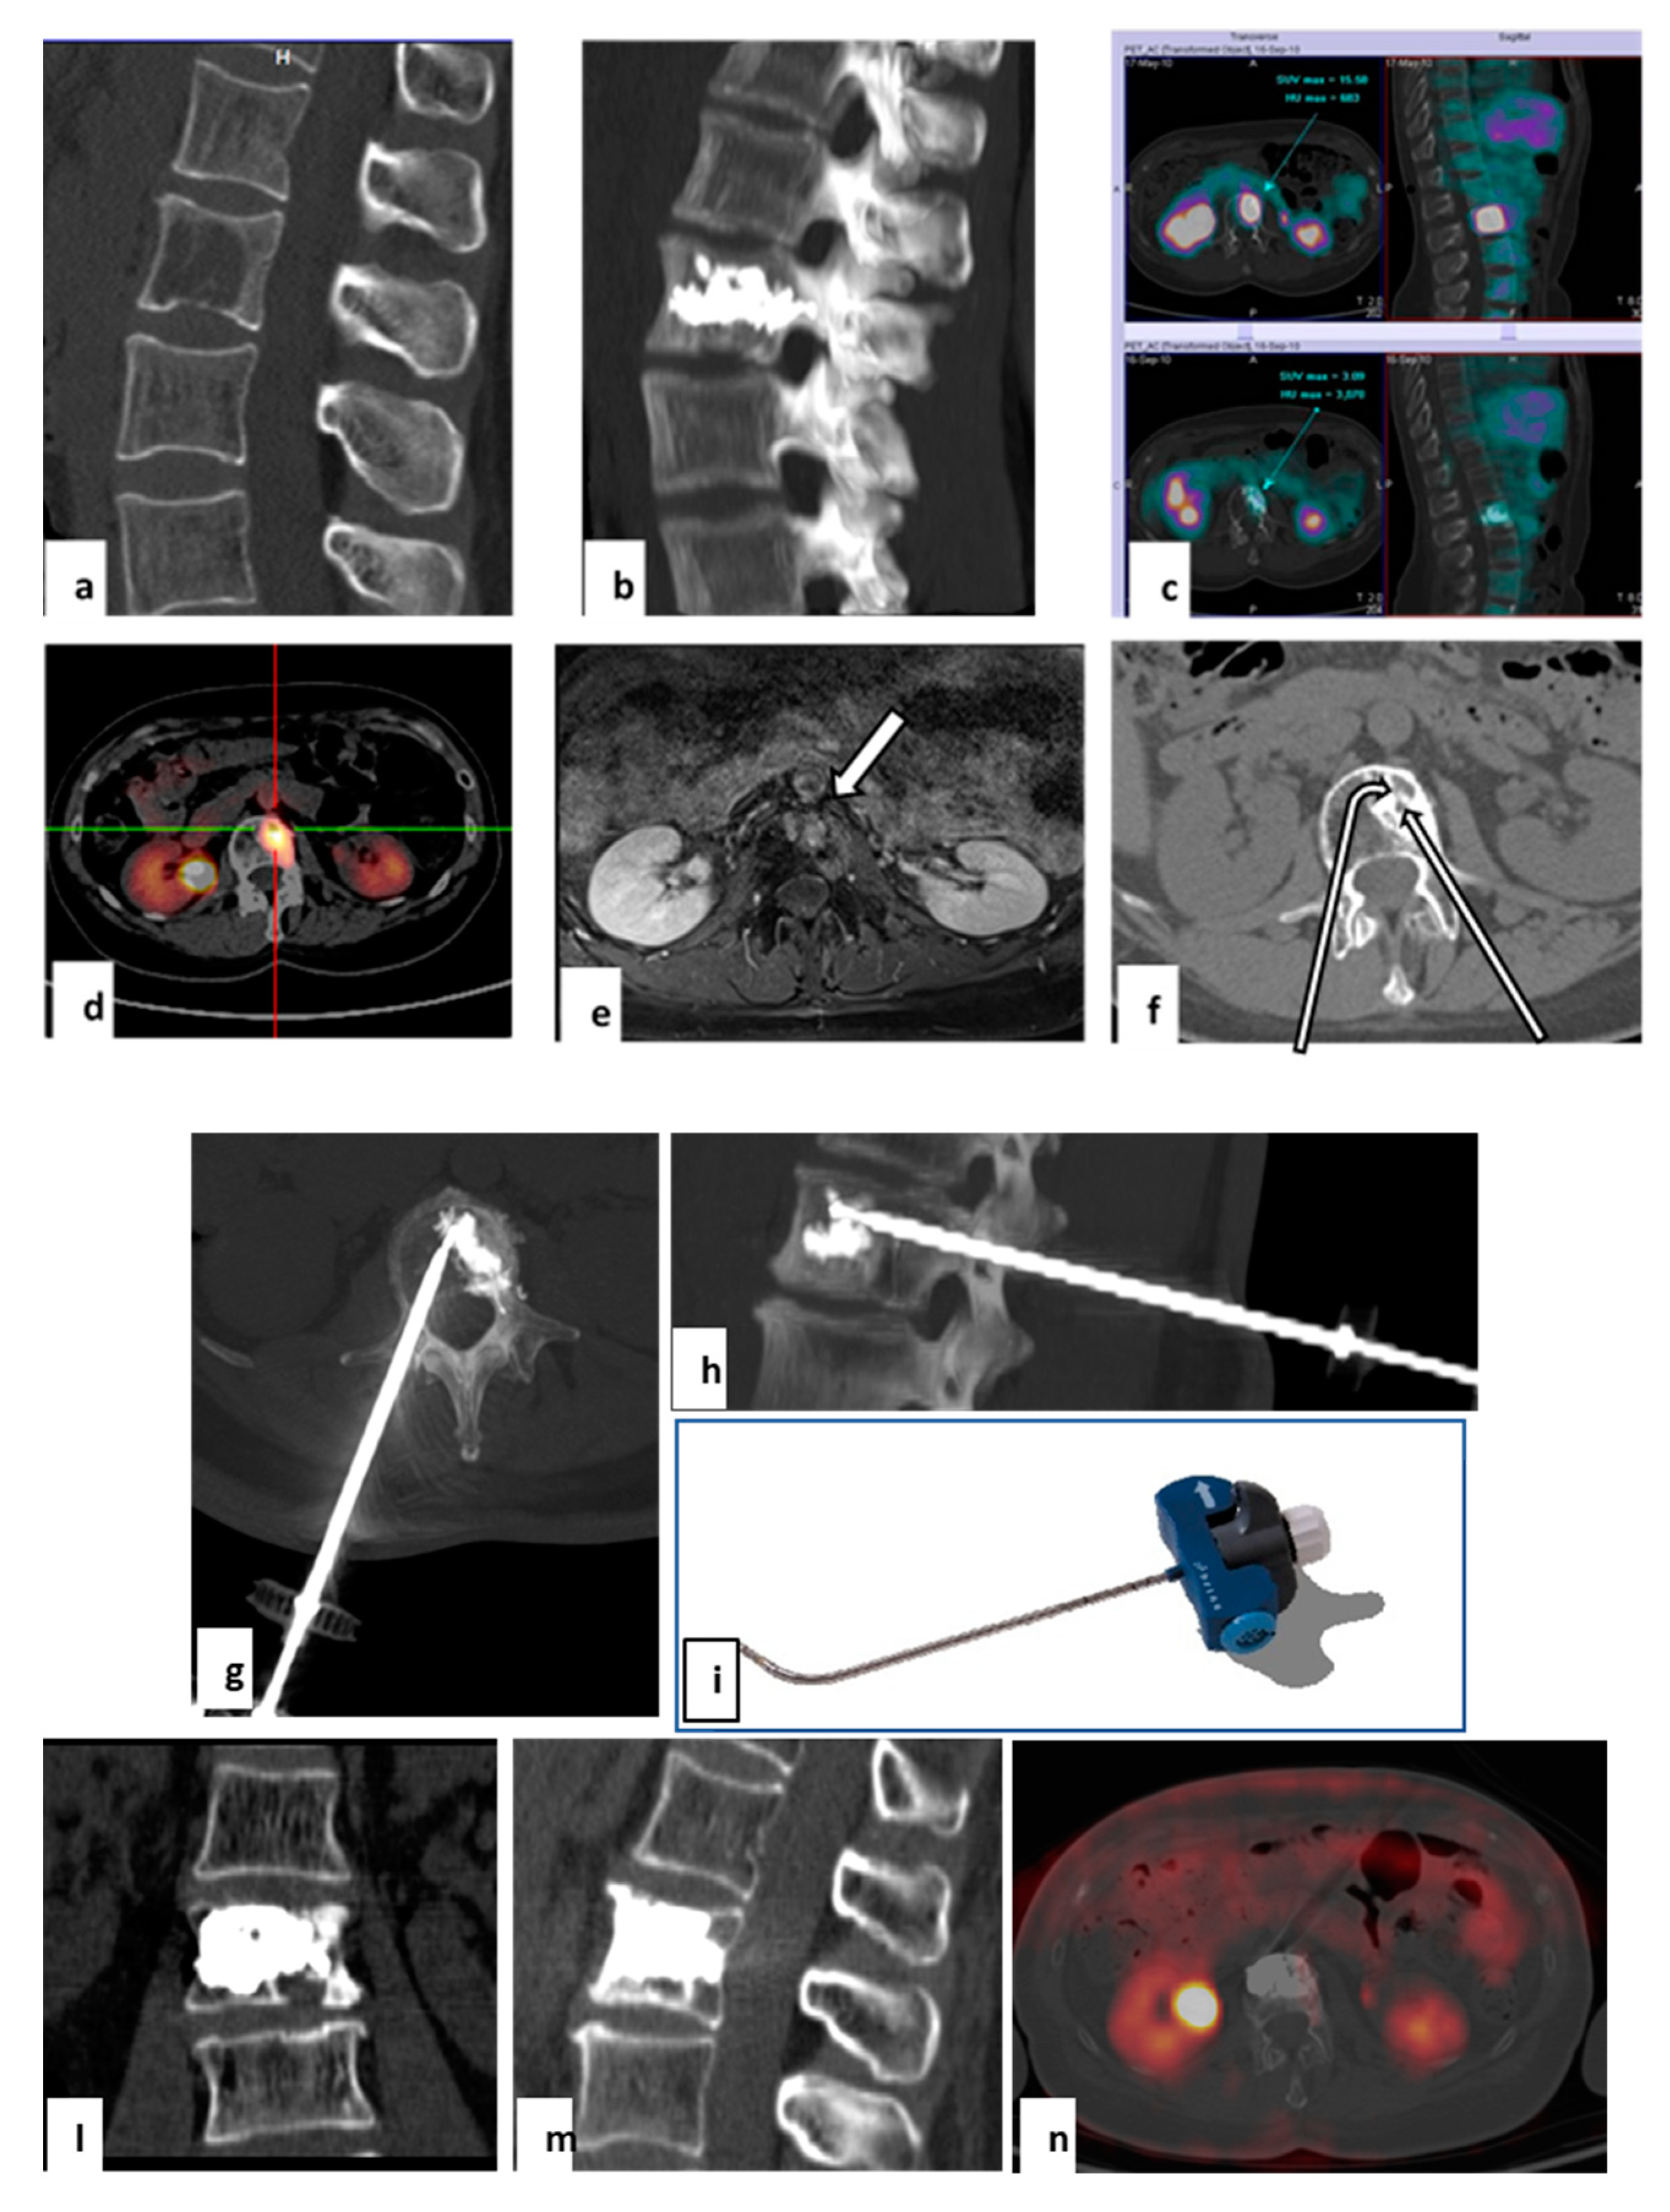

2.3. Target Radiofrequency Ablation (tRFA) and Vertebral Augmentation (VA) Procedure